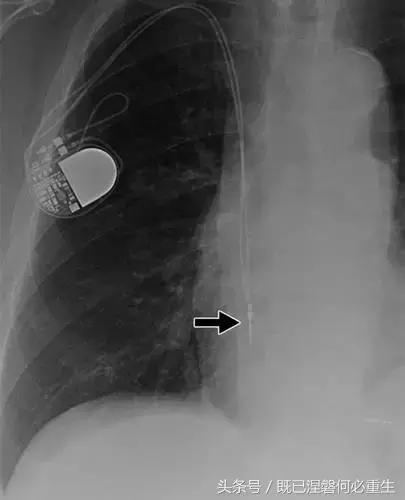

图5C,70岁女性心室穿孔。 正位胸片显示,圣犹达医疗双室起搏器的RV导联(箭头)超出心室轮廓。 心肌穿孔很少会导致放血或压塞。 患者没有受到并发症或随后的铅改变的不良影响(修订电极显示)。 心室穿孔可能导致对膜片的不适当刺激。